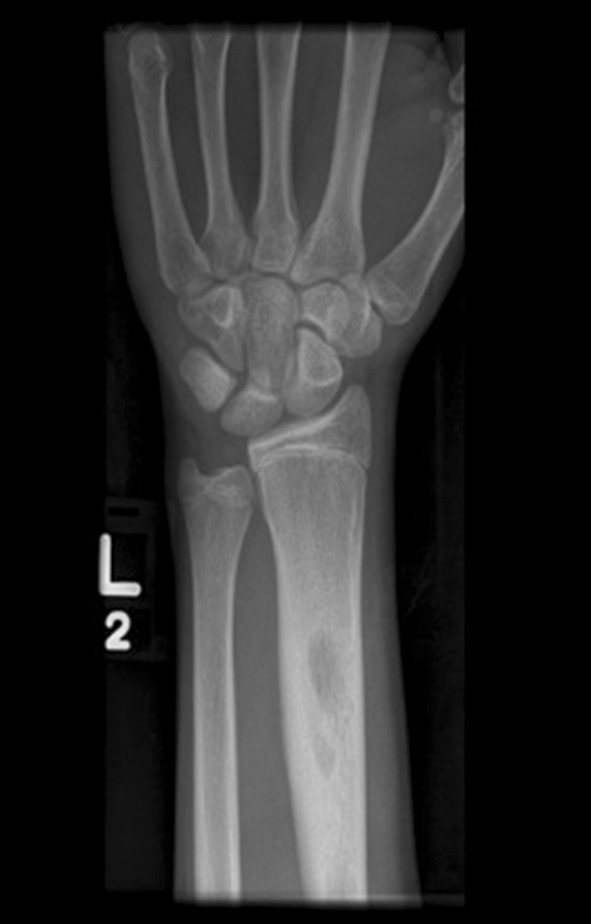

Fig. 1.

AP radiograph of the left forearm showing percutaneous K-wire fixation of a distal radius fracture